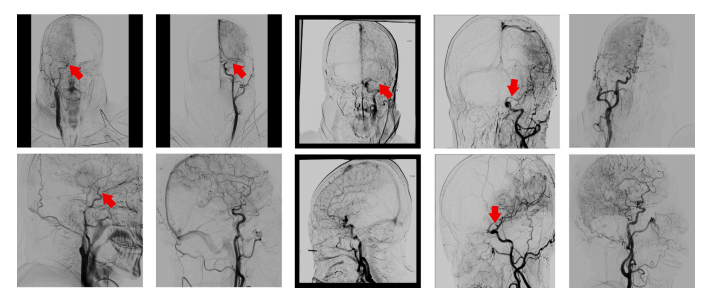

中风目前是全球主要的致死原因之一(李,2018)。其特点是高死亡率和高致残率,给医疗系统带来了沉重负担,严重威胁着公众健康。中风主要有两种类型:缺血性中风(IS)和出血性中风(HS)。缺血性中风占比75%至90%,而出血性中风仅占10%至25%(李,2018)。缺血性中风的常见病因是向大脑供血的血管阻塞,这可能会因血液灌注不足和营养缺乏导致脑细胞和组织坏死。 机械取栓术(MT)现已成为缺血性中风大血管闭塞患者的标准治疗方法(戈亚尔等人,2016),而数字减影血管造影(DSA)序列则是在机械取栓术中评估脑血管的金标准。DSA序列具有对比度分辨率高、检查时间短、低浓度下造影剂用量少以及患者接受的X射线辐射显著减少等优点。DSA成像涉及从一系列注入造影剂时获取的图像中,对未注入造影剂的X射线图像进行数字减影。通过减影、增强和重新成像过程,生成血管图像。 目前,脑梗死溶栓分级(TICI)评分是评估急性缺血性中风再灌注治疗效果的广泛使用标准,而基于DSA序列的改良脑梗死溶栓分级(mTICI)评分(扎伊达特等人,2013)也得到了广泛认可,并作为评估机械取栓术成功与否的标准评估方法。mTICI评分分为从低到高的五个等级: - T0:无灌注; - T1:顺行再灌注超过初始阻塞部位,但远端分支充盈有限,远端再灌注很少或缓慢; - T2a:顺行再灌注的范围小于先前缺血的阻塞目标动脉(例如大脑中动脉(MCA)的一个主要分支及其供血区域)的一半; - T2b:顺行再灌注的范围超过先前阻塞的目标动脉缺血区域(例如大脑中动脉的两个主要分支及其供血区域)的一半; - T3:先前阻塞的目标动脉缺血区域完全顺行再灌注,所有远端分支均无可见阻塞(扎伊达特等人,2013)。 mTICI评分越高,表示手术越成功。不同mTICI评分的示例如图1所示。mTICI与TICI的区别在于对再灌注区域进行了更详细的划分,特别是对T2b和T3再灌注的定义。扩展的TICI(eTICI)(阿尔梅赫拉菲等人,2014)进一步完善了mTICI评分系统,尤其是对T2b等级进行了更精确的细分。它增加了三个新类别:T2b50、T2b67和T2c,分别代表供血区域50%至66%、67%至89%和90%至99%的再灌注。 在当今的临床实践中,如果术后mTICI等级等于或超过2b,则认为手术成功;否则,手术失败,需要再次尝试取栓(扎伊达特等人,2013)。因此,mTICI评分是干预成功的重要指标,也是临床研究的合适终点,例如比较不同的治疗方式和评估血管内装置(布罗特和博古斯拉夫斯基,2000)。目前对mTICI评分的评估需要医生从冠状位和矢状位视觉检查DSA序列,以估计初始顺行灌注缺损有多少得到了再灌注。然而,这个过程存在观察者间和观察者内的差异,并且耗时。差异可能由医生的经验水平和检查时间长短引起。因此,一种客观且自动化的mTICI评分方法非常重要。 近年来,利用医学图像和卷积神经网络(CNN)的计算机辅助诊断技术发展迅速。在提取中风相关生物标志物方面取得了显著进展,例如从CT血管造影(CTA)图像中获取侧支循环评分(苏等人,2020)、从CT灌注(CTP)图像中获取梗死体积(罗本等人,2020)以及从CT图像中获取脑出血体积(李等人,2020)。然而,关于从DSA图像中自动提取围手术期标志物,特别是TICI评分的研究仍然非常稀少。DSA图像是与时间相关的序列,展示了造影剂在血管内的流动情况,反映了血管的狭窄或栓塞病变。因此,从DSA图像中有效提取时空特征并描绘血流速度和灌注区域的变化,是自动mTICI评分研究中的一个挑战。 尼尔森等人(2020)利用二维CNN从压缩的DSA序列中提取特征,并使用门控循环单元(GRU)(钟等人,2014)纳入时间维度进行mTICI评分。他们将时空特征解耦,先提取空间特征,然后提取时间特征,这可能会丢失DSA序列中的帧间时空特征。与此同时,autoTICI(苏等人,2021)采用了多阶段方法,包括阶段分类、运动校正和灌注分割来得出eTICI评分。虽然它是端到端的,但每个阶段的误差都会影响最终的评分性能。 因此,我们提出了CVFSNet,这是一个单阶段模型,用于自动、客观且端到端的mTICI评分。它同时从冠状位和矢状位提取时空特征,并通过探索冠状位和矢状位的位置特征生成更具代表性的特征。此外,由于缺乏包含mTICI评分标签的公开可用数据集,研究人员在进行全面研究和公正比较时受到了限制。 因此,我们在合作医院的监督下整理并发布了首个自动mTICI评分(AmTICIS)数据集。这个数据集专门为DSA序列中的自动mTICI评分而设计,旨在积极推动利用DSA图像进行的缺血性中风研究。最终,这一举措旨在为有需要的患者提供更好的医疗治疗。 总之,本文的贡献如下: (1) 我们提出了一种新颖的跨视图融合评分网络CVFSNet,用于自动mTICI评分。它同时从冠状位和矢状位提取时空特征,并通过新开发的跨视图融合模块CVFM生成更具代表性的特征。CVFM探索了冠状位和矢状位的位置特征,以实现更出色的评分性能。 (2) 为了为缺血性中风研究领域做出贡献,我们引入了一个用于自动mTICI评分的mTICI评分数据集AmTICIS。据我们所知,这是第一个带有专家标注的公开可用的mTICI评分数据集。 (3) 在新收集的AmTICIS数据集上进行的全面对比实验和二分类实验表明,与各种传统和先进的时空特征分类方法相比,我们的CVFSNet具有领先的性能。此外,在消融实验中,我们验证了新型跨视图融合模块的有效性。

Fig. 1. Top: coronal views. Bottom: sagittal views. Left to right: mTICI score T0, T1, T2a, T2b, and T3. Arrows indicate location of occlusion. By definition, T3 contains noocclusion.

图1: 上方:冠状位视图。下方:矢状位视图。从左到右:改良脑梗死溶栓分级(mTICI)评分分别为T0、T1、T2a、T2b和T3。箭头指示阻塞的位置。根据定义,T3级不存在阻塞情况。